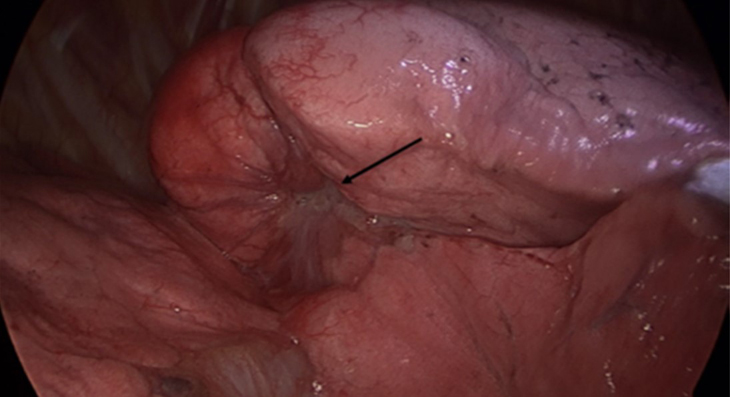

폐암 종괴의 모습